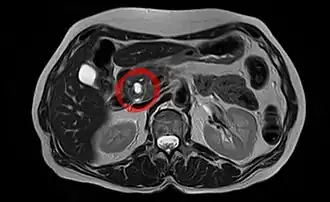

TIPMP visualisée en IRM

La tumeur intracanalaire papillaire et mucineuse du pancréas (TIPMP) est une variété de tumeur kystique du pancréas exocrine caractérisée par une dilatation du canal pancréatique principal ou des canaux secondaires.

La TIPMP se développe à partir de l’épithélium du système canalaire pancréatique et sécrète un mucus épais[1],[2],[3]. Cette sécrétion de mucus est à l’origine d’une dilatation canalaire « kystique » intéressant soit le canal pancréatique principal soit les canaux secondaires[3],[2],[1].